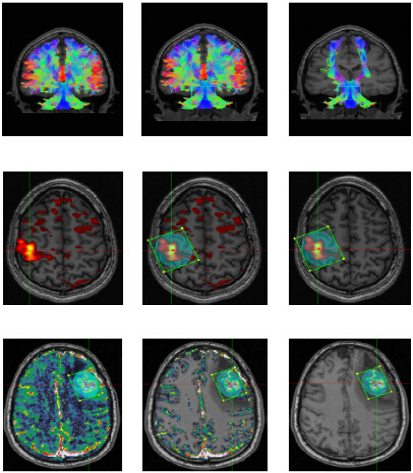

NordicBrainEx是專爲臨床設計的fMRI後處理軟件。簡易而功能強大的界面提高瞭(le)用戶的工作效率。先進的感興趣體積工具、BOLD激活區域的2D/3D可視化、DTI纖維追蹤成像和灌注MRI圖讓臨床醫生可對病竈周圍區域的大腦組織進行廣泛且深入的評估。(對於(yú)腫瘤的分類,分級,術中導航以及治療後的跟蹤監測有重要作用)

1.BOLD fMRI、DTI和DSC灌注圖像重疊(dié)在同一視(shì)圖中,擁有清晰的視(shì)圖和分析方案。

3.快速生成DTI處(chù)理後(hòu)圖像(cDTI、FA、Trace、ADC、Lambda圖)和快速纖維追蹤算法。

4.高效計(jì)算灌注圖(CBV、未校正的CBV、CBF、MTT和血管圖),包含自動(dòng)标準化、滲漏校正和血管移除算法。